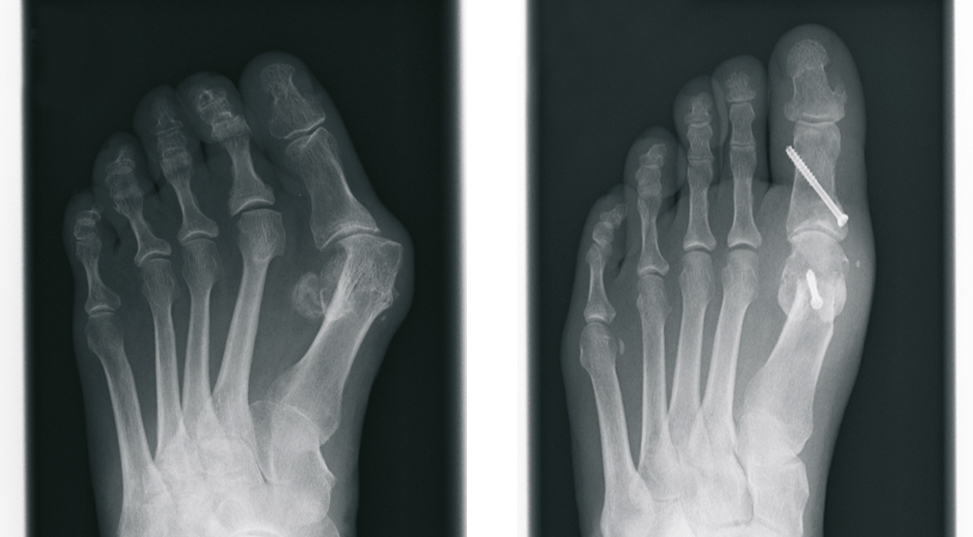

Knick-Senk-Fuß bei Kindern (Plattfuß)

Beim kindlichen Knick-Senk-Fuß handelt es sich zunächst um eine völlig normale und sogar für den Abrollvorgang beim Laufen notwendige Fußstellung. Erst ab einem bestimmten Schweregrad spricht man von einer echten Fehlstellung des Fußes. Die Stellung kann sich dabei im Laufe der Jahre während der Wachstumsphase auch von selbst bessern.

Eine krankhafte Fehlstellung kann Schmerzen, sowohl im Bereich des Sprunggelenkes und der Achillessehne, als auch im Bereich des Kniegelenkes verursachen, sogar Beschwerden im Rücken oder der Hüfte können die Folge sein. Grundsätzlich ist zunächst eine fachärztliche Untersuchung sinnvoll, eine weitere Behandlung jedoch oftmals nicht notwendig. Bei ausgeprägter Fehlstellung oder entsprechenden Beschwerden sollte jedoch eine gründliche Abklärung, einschließlich Röntgenuntersuchung in standardisierter Technik erfolgen.

Zur Behandlung steht zunächst die Einlagenversorgung und Fußgymnastik im Vordergrund, reicht diese nicht aus, muss ein operatives Verfahren in Erwägung gezogen werden.

Hierzu steht seit einigen Jahren ein modernes minimal invasives Verfahren, die so genannte Arthrorise zur Verfügung. Über einen kleinen Schnitt von nicht mehr als 2 cm, wird eine hierfür entwickelte Spezialschraube in das untere Sprunggelenk eingebracht. Wesentliche Weichteile oder Gelenke werden hierbei weder versteift noch zerstört.

Durch die Schraube kommt es zur Aufrichtung des Plattfußes. Bereits nach zwei Wochen ist eine normale Belastung möglich. Die Schraube kann nach 2-3 Jahren wieder entfernt werden, die verbesserte Fußstellung bleibt dennoch bestehen.